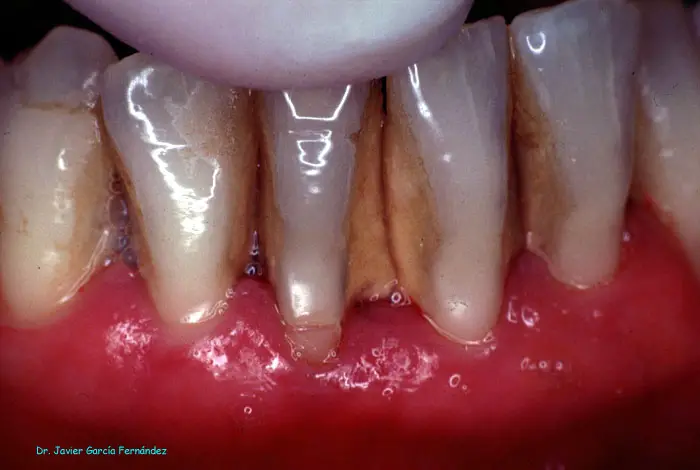

Atlas of Surgical Techniques in Periodontics. Chapter I. Diagnostic of Peridontal Diseases. Classification. Atlas de Técnicas Quirúrgicas en Periodoncia. Cap. I. Exploración y Diagnóstico. Atlas de Técnicas Quirúrgicas en Periodoncia

image154